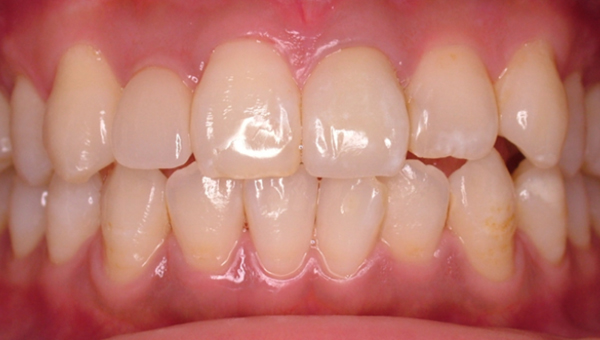

矯正前

矯正後

フルブラケットを用いた全顎の矯正治療。

3級ゴムを併用して治療

治療期間 2年2か月

治療費 600,000円+消費税

副作用 歯根吸収、むし歯、歯肉炎